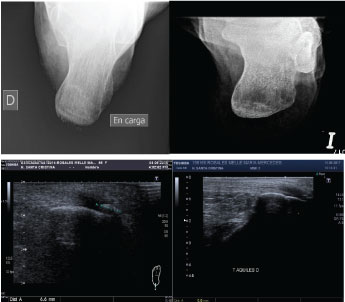

With regard to the change in millimeters (mm) of the calcification, all of the patients showed a decrease in the size of calcification. The radiological change in Achilles CT was significant; decreased from 10 ± 5.3 to 5.3 ± 5.22 mm (p = 0.0186), (Table 2, Figures 2, Figure 3, Figure 4, Figure 5 and Figure 6).

Figure 4: Case 3: In a 47-year-old male, after 20 sessions of treatment, pain decreased from 7/10 to 4/10 and size of calcification decreased from 10 to 0 mm. View Figure 4

Figure 5: Case 4: In a 57-year-old female, after 15 sessions of treatment, pain decreased from 9/10 to 4/10 and size of calcification decreased from 9 to 4 mm, evaluated by sonography. View Figure 5

Figure 6: Case 5: In a 57-year-old female, after 15 sessions of treatment, pain decreased from 5/10 to 0/10 and size of calcification decreased from 6 to 0 mm, evaluated by sonography. View Figure 6